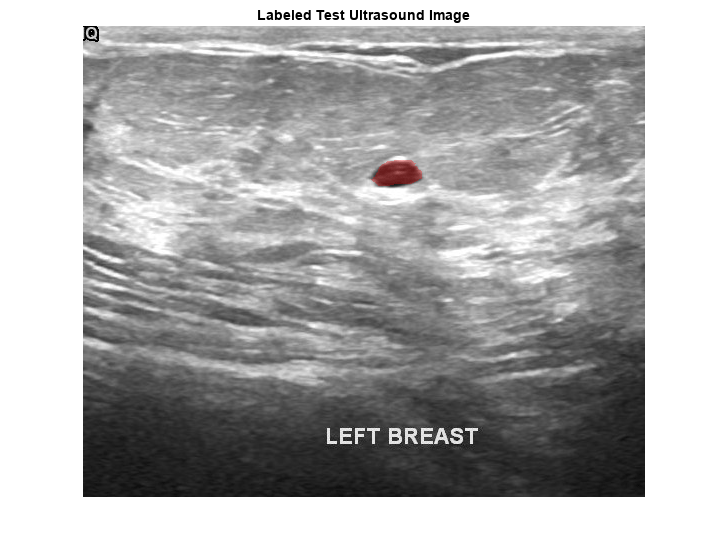

pxds = subset(pxds,contains(pxds.Files,"_mask.png"));Preview one image with a tumor mask overlay.

testImage = preview(imds); mask = preview(pxds); B = labeloverlay(testImage,mask,Transparency=0.7, ... IncludedLabels="tumor", ... Colormap="hsv"); imshow(B) title("Labeled Test Ultrasound Image")